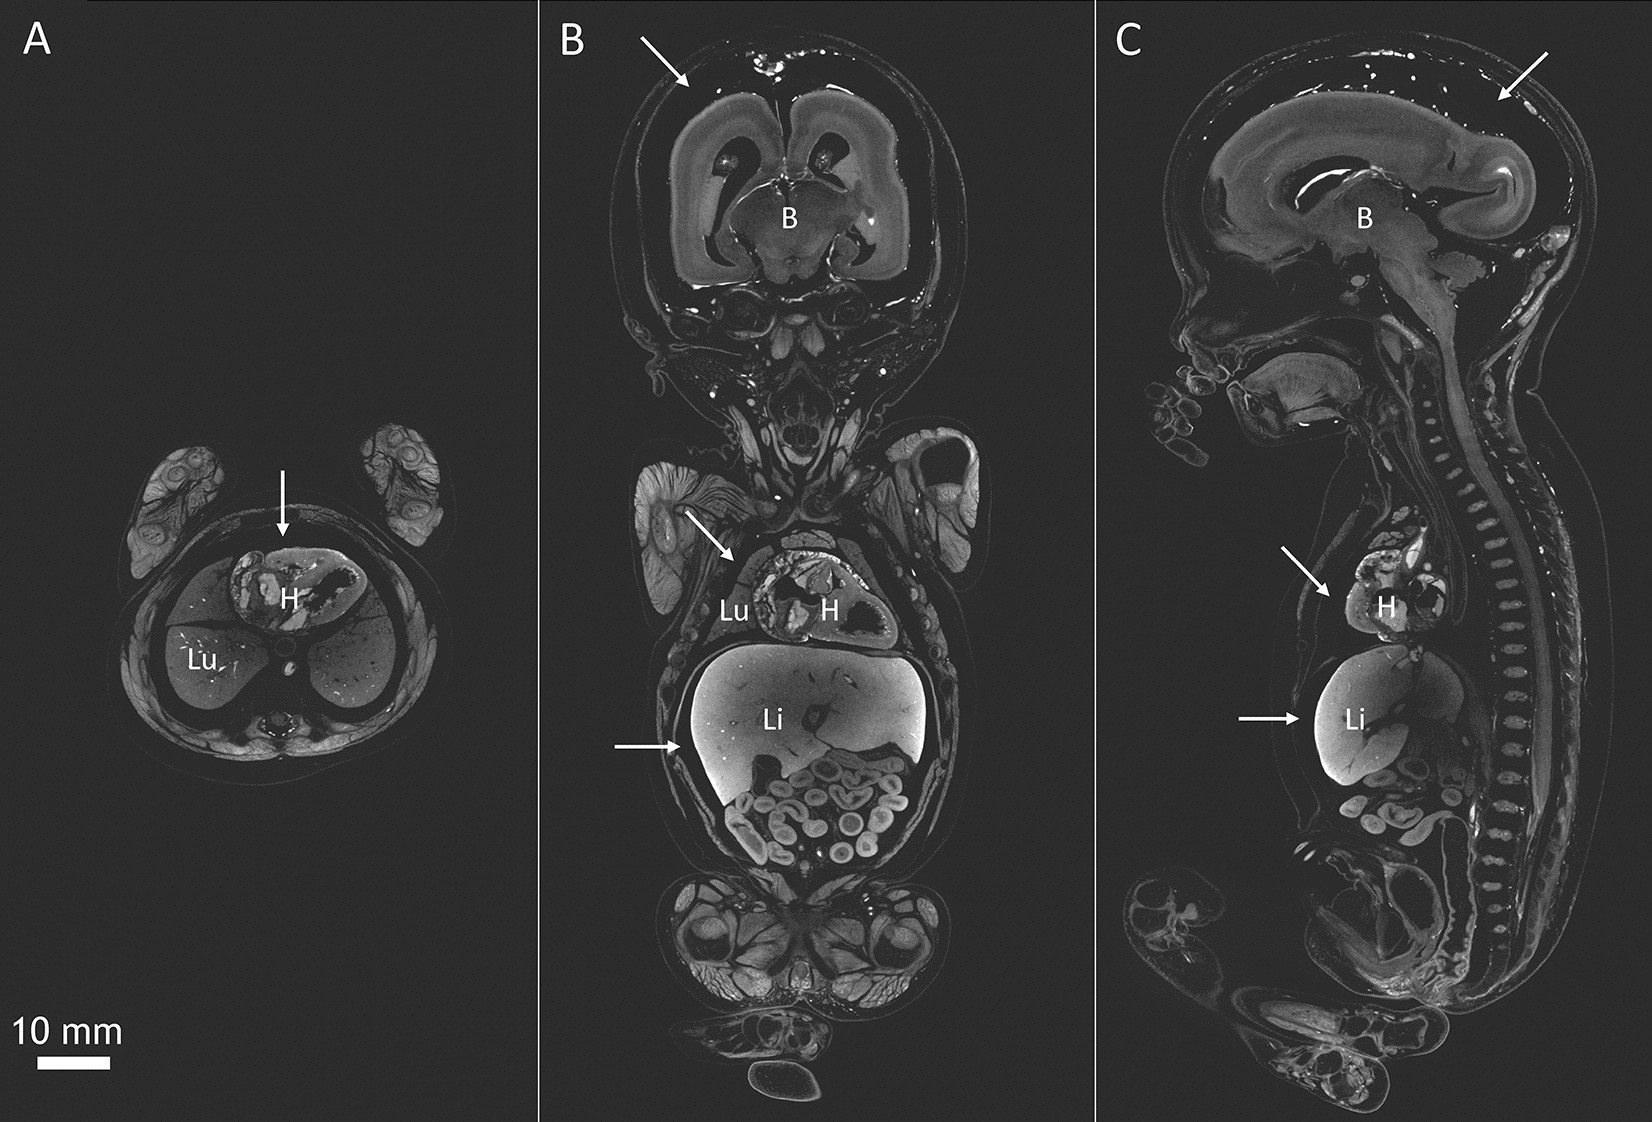

adapted from Organ specific shrinkage in iodine stained human fetuses13. White arrows point to the empty space between skull and brain and liver and body cavity, which is reminiscent of soft-tissue shrinkage. B = Brain, H = Heart, Li = Liver, Lu = Lung. Scale bar represents 10 mm.

Micro-CT images of a human fetus at 19 weeks of gestation (total length = 24 cm). The fetus was stained with 3.75% Lugol’s solution for 26 days in total. The fetus was scanned on a GE Phoenix v|tome|x scanner (General Electric, Wunstorf, Germany) with an isotropic resolution of 50 µm. (A) Transversal section at the level of the heart, (B) mid coronal section and (C) mid sagittal section. Volume analyses showed that the staining caused extensive shrinkage: 9% in total fetal volume, 24% in lung and liver volume, 31% in kidney volume and 33% in brain volume Images